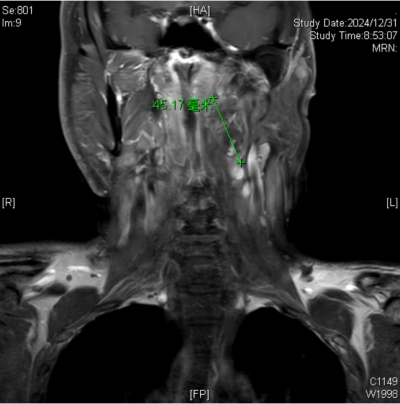

的耳鼻咽喉头颈外科就诊。接诊的杨中纯副主任医师通过颈部增强磁共振成像(MRI)检查,最终确诊导致王永元咽部不适的罪魁祸首竟是咽旁后间隙肿瘤,紧邻口咽部。入院后,经过颈部CTA检查,发现肿瘤将颈内动脉推挤至外侧、变形,经过仔细阅片和详细的术前讨论,耳鼻咽喉头颈外科的医生团队制定了周密的手术计划。

颈部增强磁共振成像(MRI)下发现导致王永元咽部不适的罪魁祸首是咽旁后间隙肿瘤